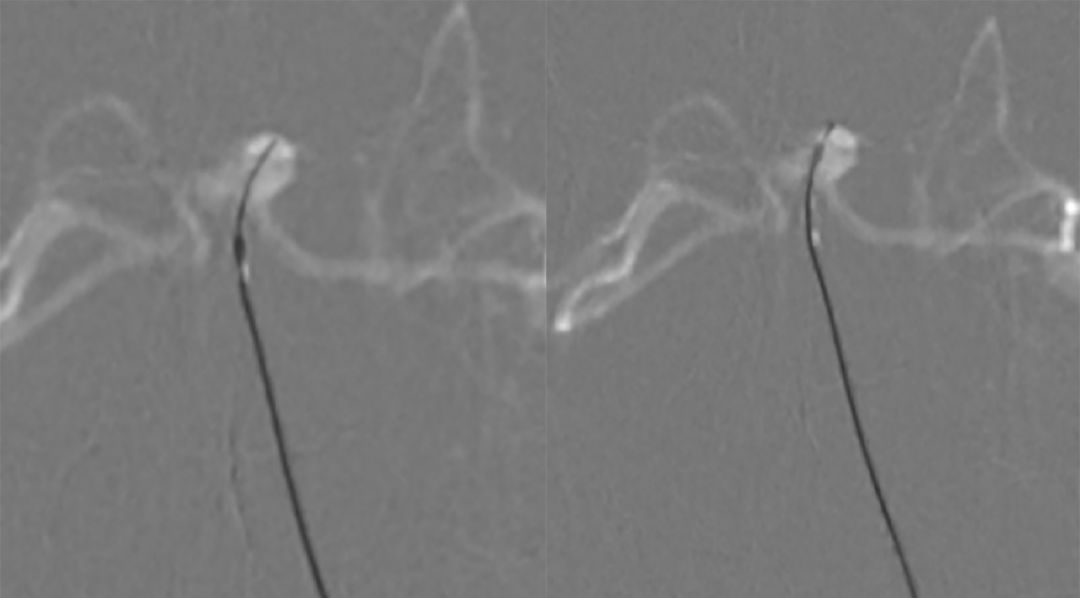

2. 将Echelon-10微导管置入基底动脉较粗的管腔中进行微量造影(正位、侧位)(图6):左侧大脑后动脉显影。

图6

3. 再将Echelon-10微导管置入基底动脉较细的管腔进行微量造影(正位、侧位)(图7):双侧大脑后动脉及左侧小脑上动脉显影,可见动脉瘤位于左侧小脑上动脉。

图7

4. 最后将Echelon-10微导管置入基底动脉中下段进行微量造影:基底动脉2个管腔、 双侧大脑后动脉显影、小脑上动脉均可显影(图8)。

图8